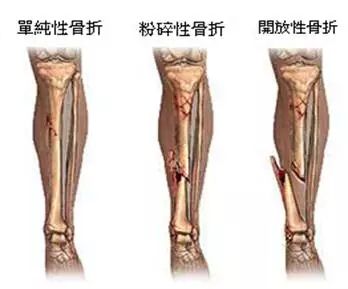

1、外伤骨头——粗看X光片、细看CT

各种外伤,如果怀疑伤到了骨头,优先选择X光照片,检查结果快速易得。若要进一步观察,可以选择CT。超声、核磁对于骨皮髓质等看不大清,一般不选择。